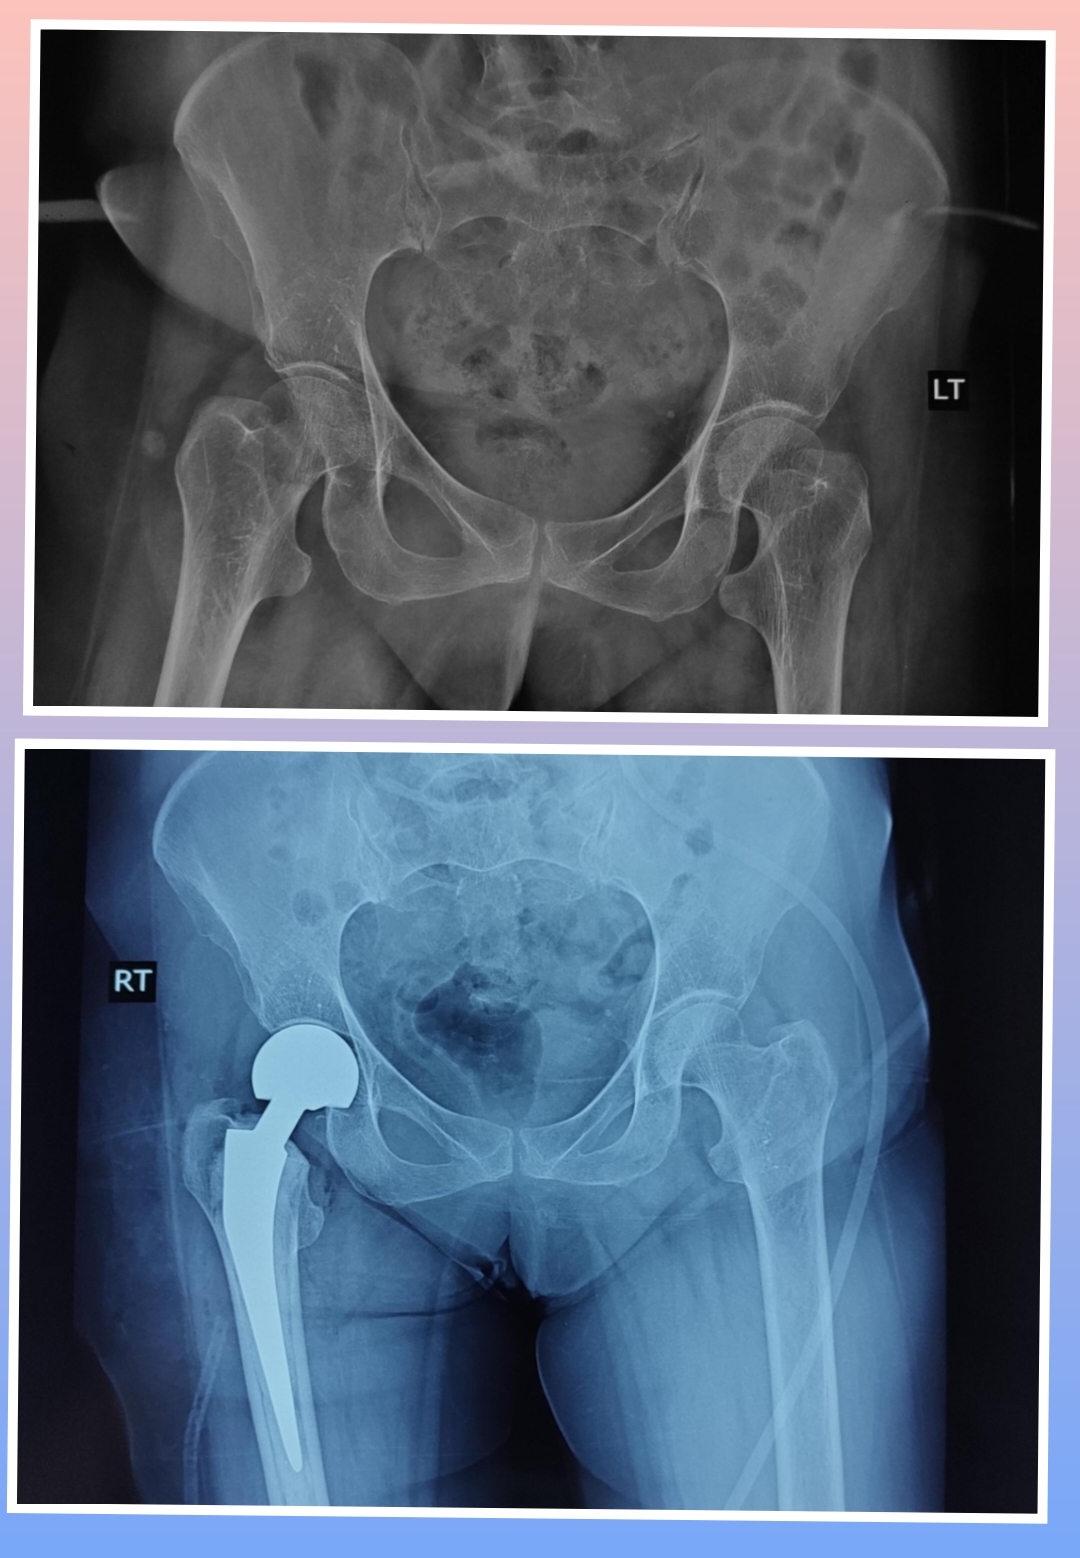

Warning: Graphic Content

The following section contains graphic images of surgical procedures. These images are intended for educational purposes and may be disturbing to some viewers. Viewer discretion is advised.

Surgeries